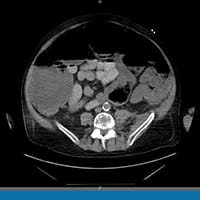

Todos os outros exames laboratoriais estão normais. É feita uma radiografia de abdome. O paciente é internado por causa dos seus exames. Uma tomografia computadorizada (TC) de abdome e pelve sem contraste é feita na sequência. Os achados dos exames de imagem são mostrados abaixo (Figuras 1 a 4).